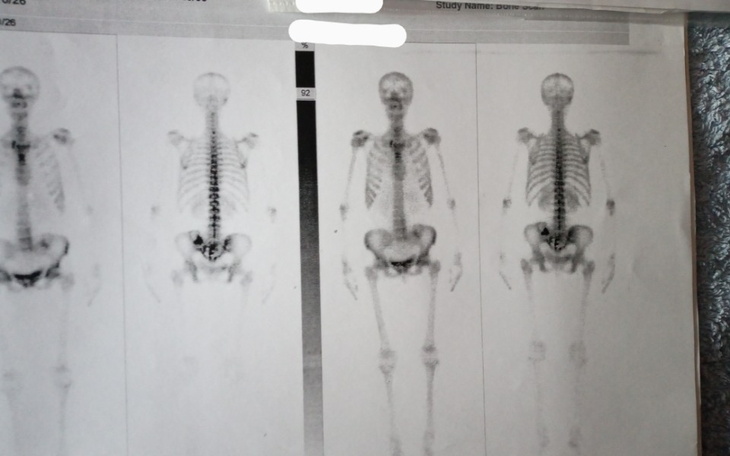

Drodzy państwo wszyscy mamy swoją własną historię. Każdy z nas zmaga się z wieloma zmartwieniami, chorobami i trudnym życiem. Od 19 lat choruje na nowotwór,

obecnie zaatakowany jest cały organizm

Zmierzyłam się z wieloma operacjami i radioterapią która po wielu latach leczenia przyniosła negatywne skutki oparzeń organów wewnętrznych.

Dołączam dokumentację medyczną jednak jest ona zbyt duża aby w całości ją tutaj zmieścić. (kilka teczek)